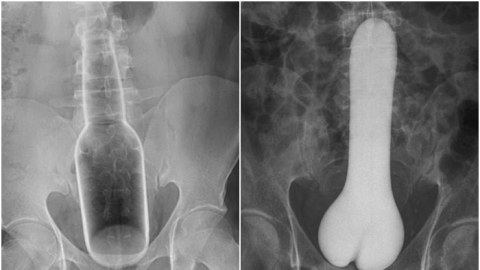

รวมภาพ X-Rays แปลกๆจากห้องฉุกเฉิน ที่หลายคนถึงกับงงว่ามันเข้าไปในก้นของพวกเขาได้ยังไง?